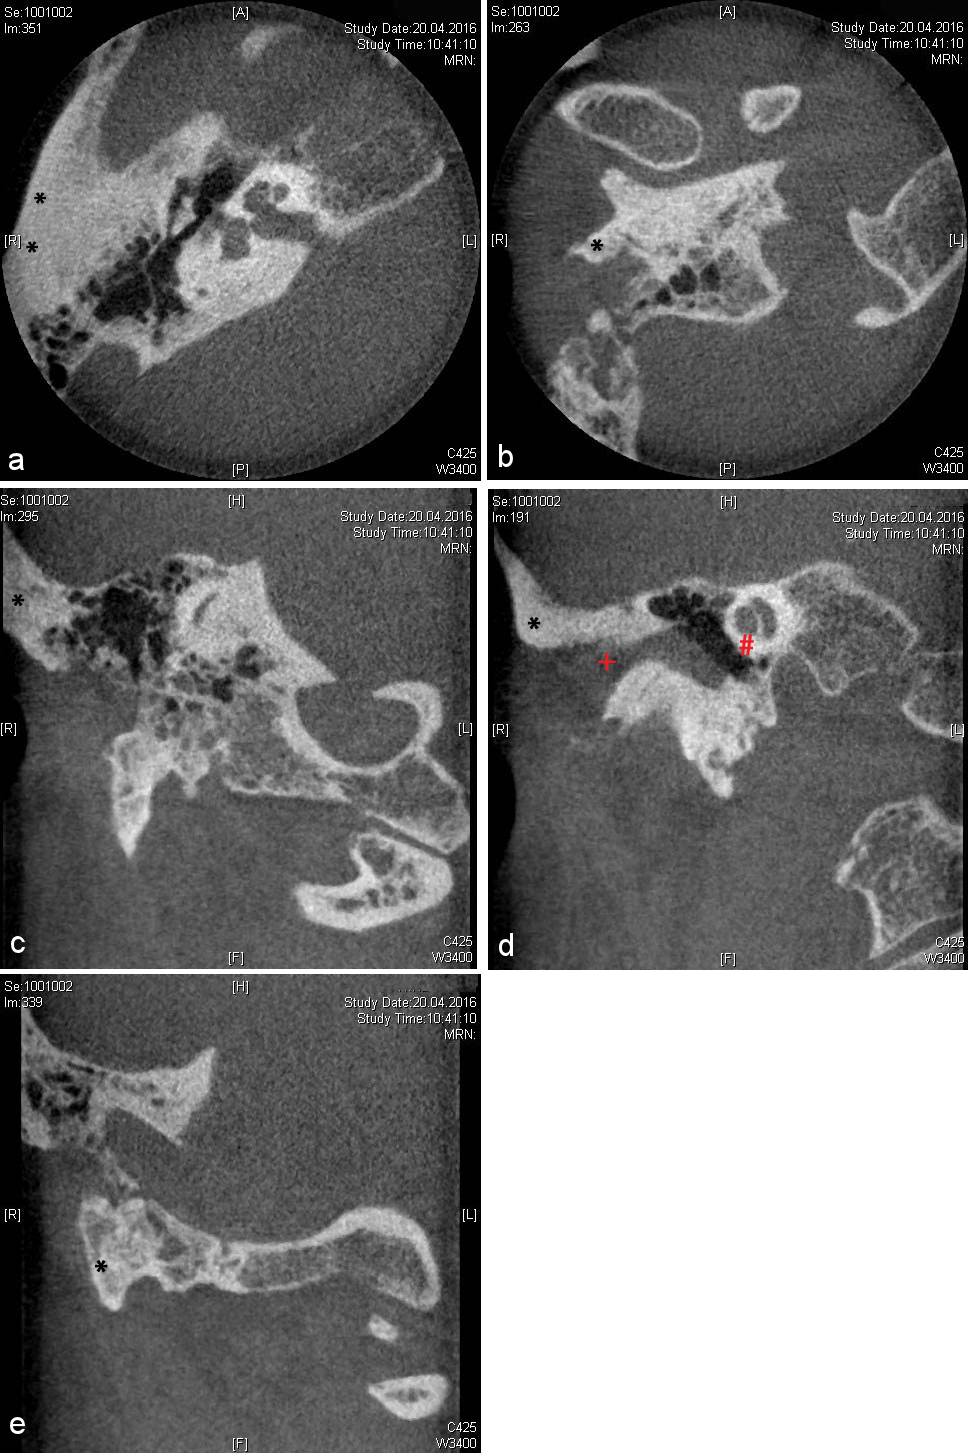

Following a recurrence free interval, the patient was supplied with a temporary adhesive-retained epithesis (B-400 Secure medical adhesive, Daro B-200-30 adhesive, Cosmesil, Heidelberg, Germany). This epithesis covered the residual cranial concha, thereby providing undercuts and an additional retentive surface (Figure 3 [Fig. 3]). The definitive epithetic treatment was then conducted following 3D preoperative assessment involving cone beam computerized tomography (CBCT) of the temporal bone (Figure 4 [Fig. 4]).

Figure 4: Preoperative cone beam computerized tomography (CBCT) imaging. a: Axial section. Black asterisk indicating planned cranial implant positions. b: Axial section. Black asterisk indicating planned caudal implant position. c: Coronal section. Black asterisk indicating planned first cranial implant position. d: Coronal section. Black asterisk indicating planned second cranial implant position, red plus marking the external meatus acusticus, and red diamond showing the cochlea. e: Coronal section. Black asterisk indicating planned caudal implant position.